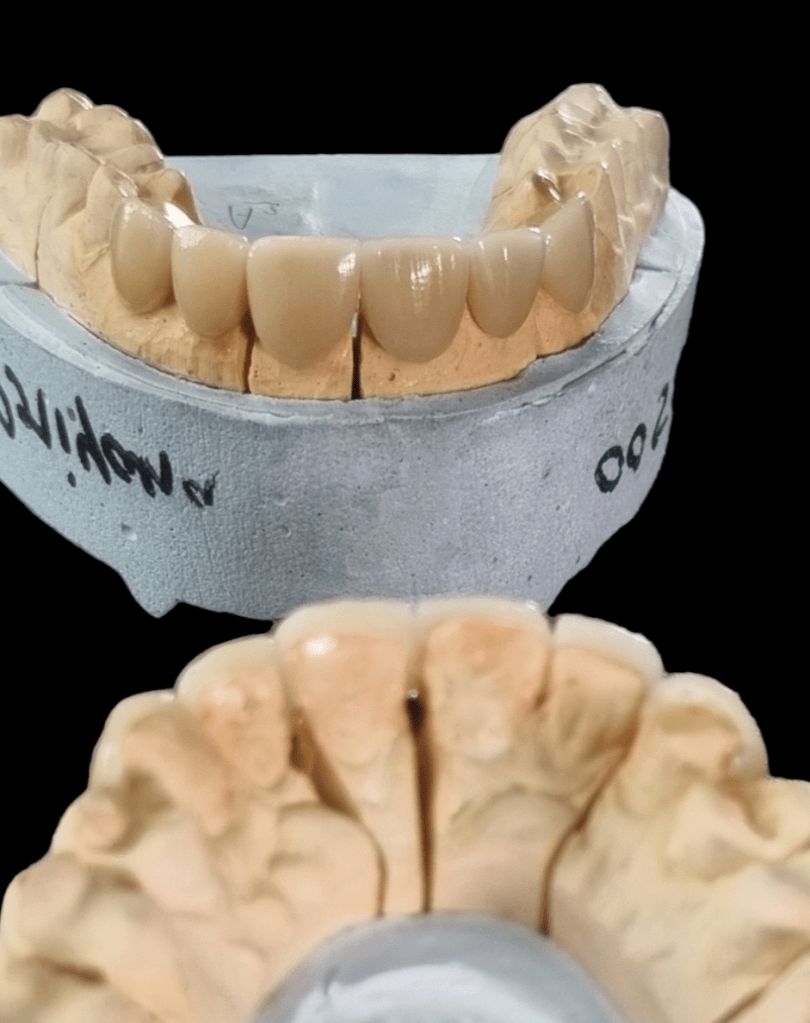

The picture gallery at Gracious Smiles showcases some of the remarkable transformations our patients have achieved through the range of dental treatments. From before-and-after photos of dental implants, Invisalign aligners, and braces to images of successful TMJ treatments, the gallery provides a visual representation of the high-quality care that patients can expect at Gracious Smiles. The photos are a testament to the expertise and dedication of our dental professionals in helping patients achieve their dream smiles.

Ceramic Veneers